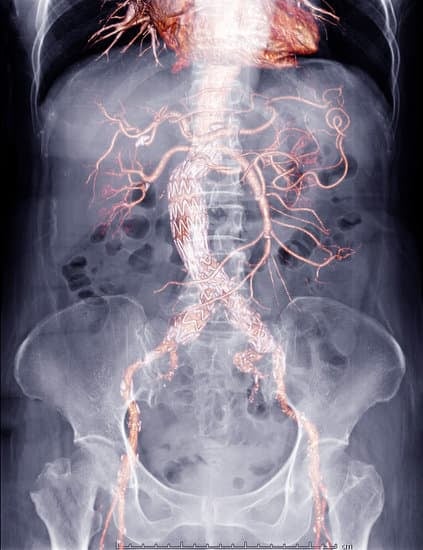

CT 스캔: 혈관의 구조를 정밀하게 볼 수 있어 대동맥류의 크기와 위치를 정확하게 평가할 수 있습니다.

개복 수술: 대동맥의 손상된 부위를 인조 혈관으로 교체하는 방법입니다.

혈관 내 수술(EVAR): 덜 침습적인 방법으로, 대퇴동맥을 통해 스텐트 그라프트를 삽입하여 대동맥류 부위를 덮어 파열을 방지합니다.